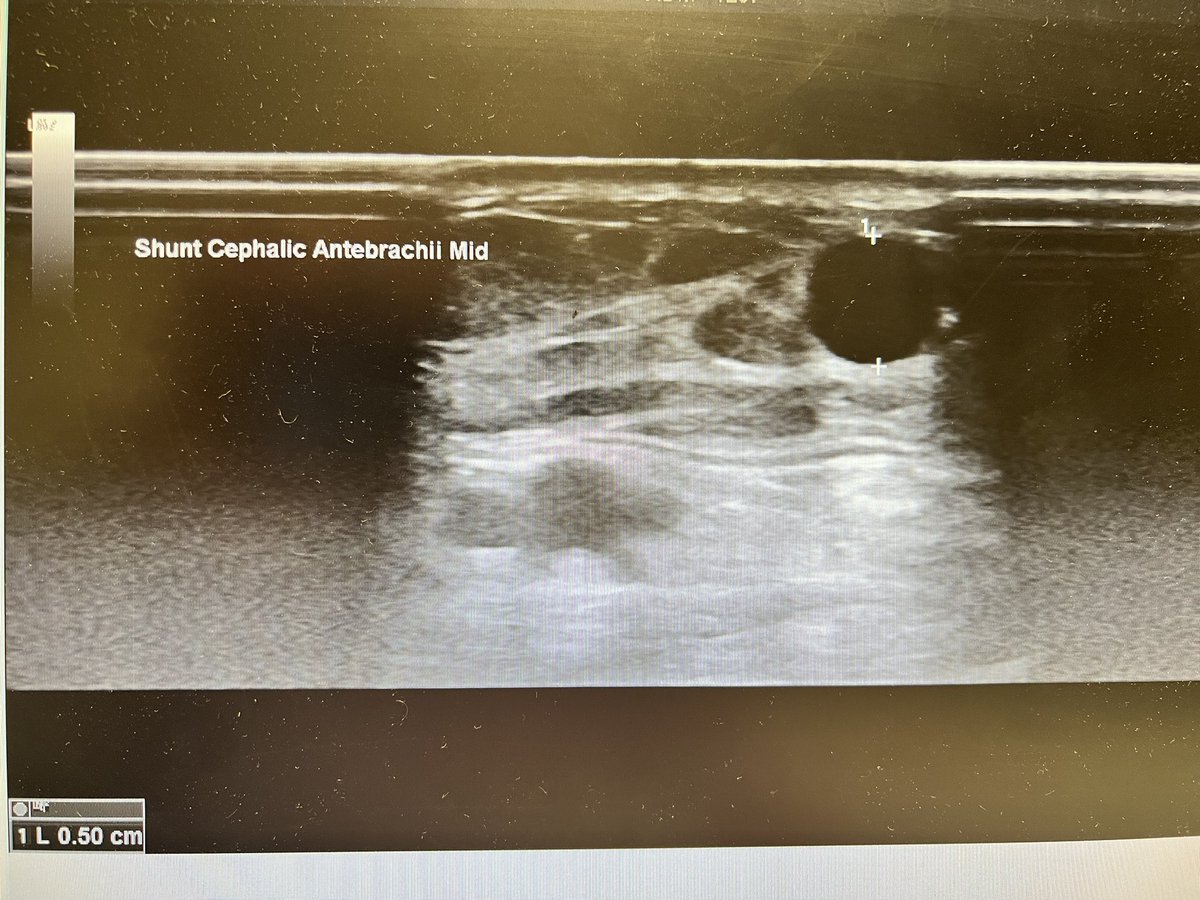

Brachial artery and mid level forearm cephalic vein before (fig 1-2) and exactly 2 days!!!! after (fig 3-4) the creation of a

#VasQ#RCAVF in a#CKD patient@wasse_m@jimbog_76@OBaumgaertner_#VascularAccessCenter#Hamburg#Barmbek#LaminateMedicalpic.twitter.com/0aX0710Wnu